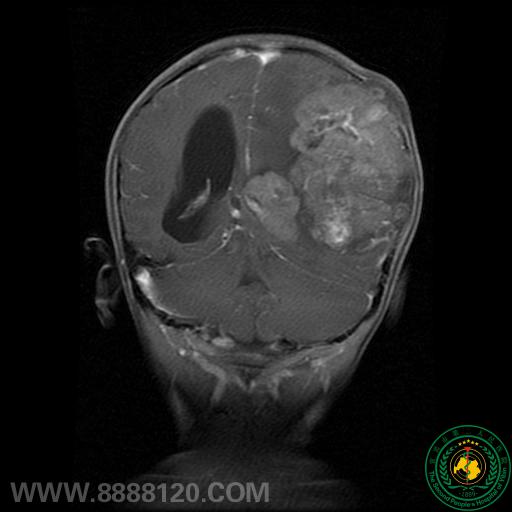

我科完成儿童颅内半球巨大室管膜瘤一例

我科完成儿童颅内半球巨大室管膜瘤一例5209